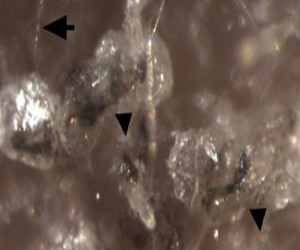

أعلن معهد علمى بارز فى اليابان اليوم الثلاثاء، أنه خلص إلى وجود بيانات مزورة فى بحث بشأن الخلايا الجذعية قامت به مجموعة من العلماء. واتهم معهد "ريكن" الذى تموله الحكومة، كبيرة الباحثين "هاروكو أوباكاتو" من مركز التنمية البيولوجية التابع للمعهد، بأنها المسئولة عن هذا الخطأ. وخلصت اللجنة التابعة للمعهد إلى أن "أوباكاتو" قامت بالتلاعب أو تزوير مجموعتى صور للحمض النووى (دى إن إيه) نشرتهما دورية "نيتشر" البريطانية فى يناير الماضى. ووصفت "أوباكاتو" ما توصلت إليه اللجنة بأنه غير مقبول، قائلة: "إنى مفعمة غضبًا ودهشة". وقال معهد ريكن، إن هناك ثلاثة أشخاص شاركوا فى البحث لم يقوموا بتزوير البيانات، ولكنهم مسئولون "بصورة كبيرة" عن عدم التحقق من المحتوى. وقد خلص الفريق بمعهد ريكن وجامعة هارفارد إلى وجود وسيلة جديدة لتخليق خلايا جذعية بطريقة أكثر سهولة وسرعة بغمسها فى حامض. وحازت هذه الدراسات اهتمامًا عالميًا، ولكن أثيرت تساؤلات حول وجود عدد من الأخطاء بها، ومنها الصور المستخدمة فى البحث.